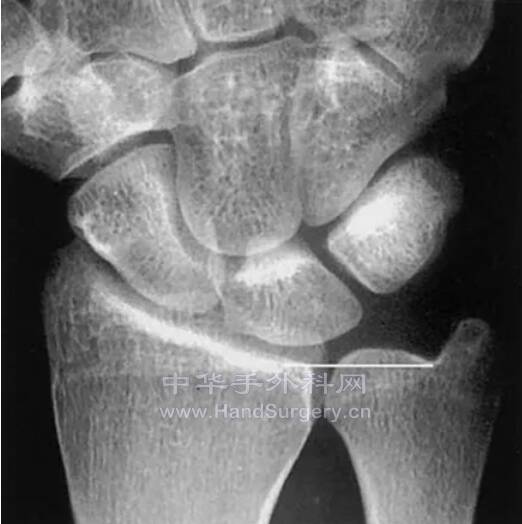

如上所述拍出来的X线片(即拍正位和侧位片前臂均处于旋转中立位)

正位片上尺骨茎突在尺侧,侧位片上尺骨茎突也在尺侧

微信截图_20220520233226.png

微信截图_20220520233321.png